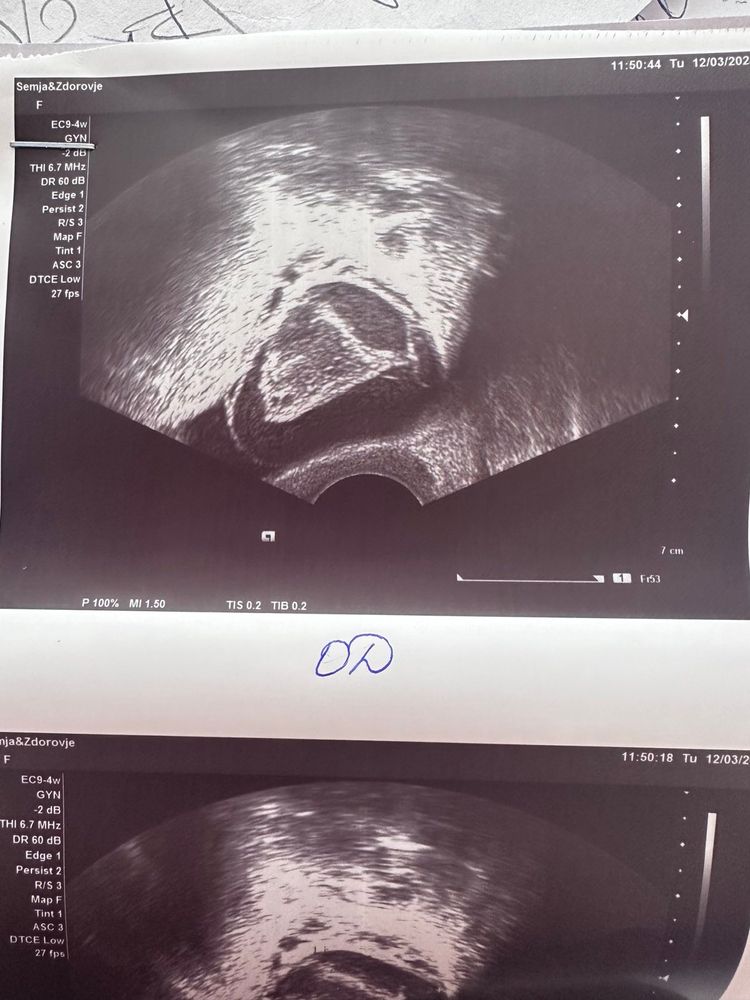

Я 2-й день пытаюсь разобраться с кистой. По узи незначительная жидкость, эндометрий секреторный 9,1 мм и киста 33х38 мм. Какая киста, мне так и не сказали. Бт странная, по ней тоже понять что-то сложно. 3 дня тесты на овуляцию были положительные.

Перечитала весь интернет и поняла, что по снимку очень сложно отличить кисту ЖТ и фолликулярную. Может у кого-то есть снимки кист и их основные отличия?

повторно прикреплю снимки, может кто-то сможет мне помочь. Буду благодарна любым ответам.

Алина , так как самого заключения УЗИ я не вижу, основываясь на Вашем описании и снимках, с больше долей вероятности можно предположить что овуляция была с образованием кисты ЖТ, что бывает часто.

В описании УЗИ должны были указать что за киста. Основываясь на данных о секреторном эндометрии и наличии свободной жидкости, можно предположить что это киста ЖТ

Юлия , спросила может ли это быть киста желтого тела, узист пожала плечами, написано просто гипоэхогенное образование. т.е. она просто сказала "киста". Неделю назад был доминантный фолликул 16 и через пару дней полосатые тесты на овуляцию.